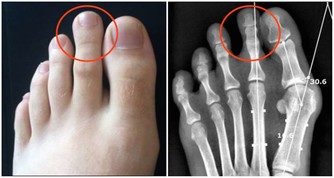

4、腰酸背痛、腰酸背痛不僅是男人出現的問題,女性也是經常有,尤其是到了一定的年齡階段,而這一癥狀的出現,人們也能很快的聯想到腎臟可能出現了問題。《素問。六節臟象論》中有說:「脊者....其充在骨」,說明骨髓的功能得以維持的能量來源於腎臟,骨髓由腎精所化生,《素問‧陰陽應像大論》中也強調:「腎主骨髓。」因為腎藏精,而精生骨髓,骨髓充實,骨骼強壯,運動捷健。所以說腎的精氣盛衰,直接影響骨骼的生長、營養、功能等。

所以腎氣衰敗很容易出現骨質疏鬆、腰酸背痛,甚至是牙齒出現鬆動等癥狀。